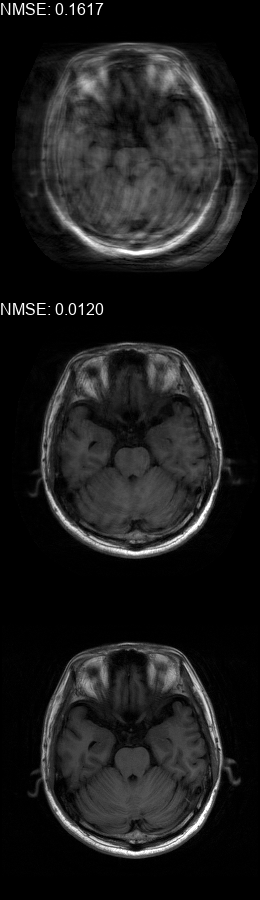

Fig. 5 contains four scan reconstructions from two patient cases. In both cases, the patient was requested to move at a certain time. In order to provide a ground truth for this scenario, another scan was performed using the same protocol for each patient, where the patient was required to hold still. The motion timing information for this case was obtained using the method described in [2] as it requires no additional hardware or changes to the scan protocol. We compare the reconstruction error using the SSIM [17] and the Visual Information Fidelity (VIF) [16] metrics, since a pixelwise comparison is not viable in this case.

Figure 5: Examples of real motion corrupted images together with their motion corrected counterparts. The bottom row shows a corresponding slice from a motion-free acquisition of the same subject. These motion-free images were acquired using an additional scan. The images on the top row are motion-corrupted. Images on the middle row were corrected using our method. (a,b) motion was was detected at t1=96subscript𝑡196t_{1}\!=\!96, (c,d) the motion was detected at t1=112subscript𝑡1112t_{1}\!=\!112. All scans were acquired using 𝒮260subscript𝒮260\mathcal{FS}_{260} presented in Fig. 1b.